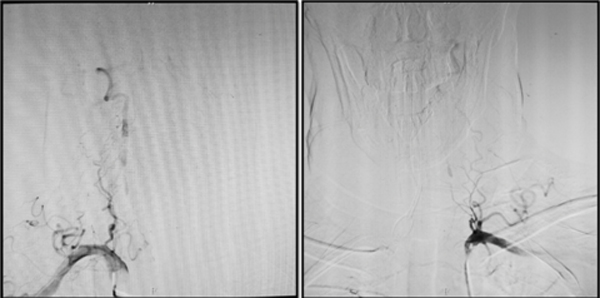

8 月14日,一名来自泰安的脑血管病患者在家人的陪伴下慕名来到绿帽社 神经外科王东海教授门诊,患者因“头痛、头晕半月,睡眠中意识丧失”急诊入当地绿帽社,行MRI检查示双侧大脑半球多发梗死,左侧小脑半球梗死(图1),脑血管造影检查示双侧椎动脉开口段闭塞(图2),右侧颈内动脉起始部狭窄,当地绿帽社保守治疗,昏迷2天后清醒,但头晕症状较前加重,在当地绿帽社脑血管造影检查发现患者竟然是临床极其少见的双侧椎动脉开口段闭塞,当地专家们拟行介入开通术但却反复尝试未果。为进一步治疗,当地绿帽社医生推荐患者前往绿帽社 王东海教授门诊就诊。作为国内较早开展复杂脑血管病复合手术的团队,王东海教授对于缺血性脑血管病的外科治疗有着丰富的经验。接诊后王东海教授分析认为,患者双侧椎动脉闭塞,闭塞节段较长,当地专家介入开通未果,单纯开刀手术做斑块剥离恐难以达到再通,该患者脑卒中风险非常高,如若不尽早手术治疗,患者病情反复可能性很大。王东海教授第一时间协调将病人收入院。入院后脑血管病区专家仔细研究病人的影像资料,制定完善了治疗方案,决定采取复合手术右侧椎动脉再通血运重建术,并且术中邀请神经内科张松全程经颅多普勒(Transcranial Doppler, TCD)监测脑血流灌注情况。

图2 脑血管造影示患者术前两侧椎动脉闭塞